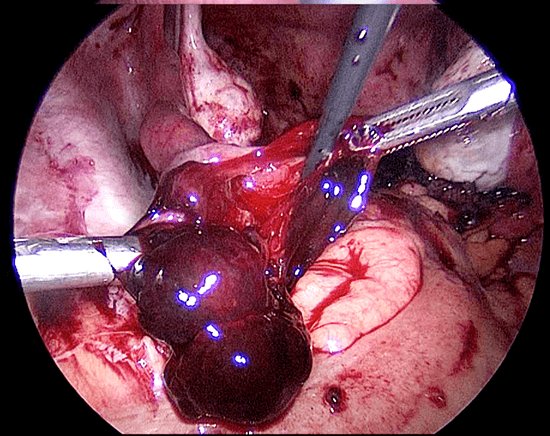

Reseksi laparoskopi kornu kehamilan ektopik

Pada tahun 2009 nyonya UDS datang mengunjungi saya , dia telah menikah 3 tahun dan dia tidak bisa hamil. Histerosalpingogram yang dilakukan di rumah sakit yang lain menunjukkan kedua tubanya tersumbat / terblokir. Dia menjalani laparoskopi , dan laparoskopi menunjukkan ukuran rahim yang normal. Kedua tuba nya normal dan dipatenkan setelah insulfasi tuba dilakukan dibawah tekanan. Dia hamil secara spontan 2 bulan setelah menjalani laparoskopi namun sayangnya kehamilan berakhir dengan aborsi yang terlewatkan. Dia telah menjalani evakuasi hasil konseptus. Pasca operasi , keadaan dia baik-baik saja akan tetapi tidak dapat hamil. Dia telah diberikan beberapa siklus klomifen sitrat namun tanpa membuahkan hasil. Pada tahun 2011, dia menjalani siklus inseminasi intrauterin setelah diberikan suntikan hormon perangsang folikel ( FSH ). Setelah prosedur dilakukan , dia hamil akan tetapi sayangnya kehamilan itu adalah kehamilan ektopik. Dia menjalani reseksi laparoskopi kornu kanan kehamilan ektopik di tahun 2011 ( Gambar 26.7 – 26.11 ) ( simak video 26.3 ). Pasca operasi di tahun 2013 dia menjalani histerosalpingografi dan menunjukkan bahwa tuba kiri tidak paten. Dia dapat hamil setelah menjalani IVF.

Pembahasan

Kornu kehamilan ektopik tidaklah umum. Biasanya didiagnosisnya terlambat karena pasien dengan kondisi seperti ini tidak memliki banyak gejala-gejala. Pecahnya kehamilan ektopik pada kornu dapat menyebabkan pendarahan yang berlebihan. Pada pasien ini diagnosis dilakukan lebih awal karena dia menjalani IUI dan berada dalam pengawasan secara teratur. Eksisi telah dilakukan dengan berhasil secara laparoskopi.